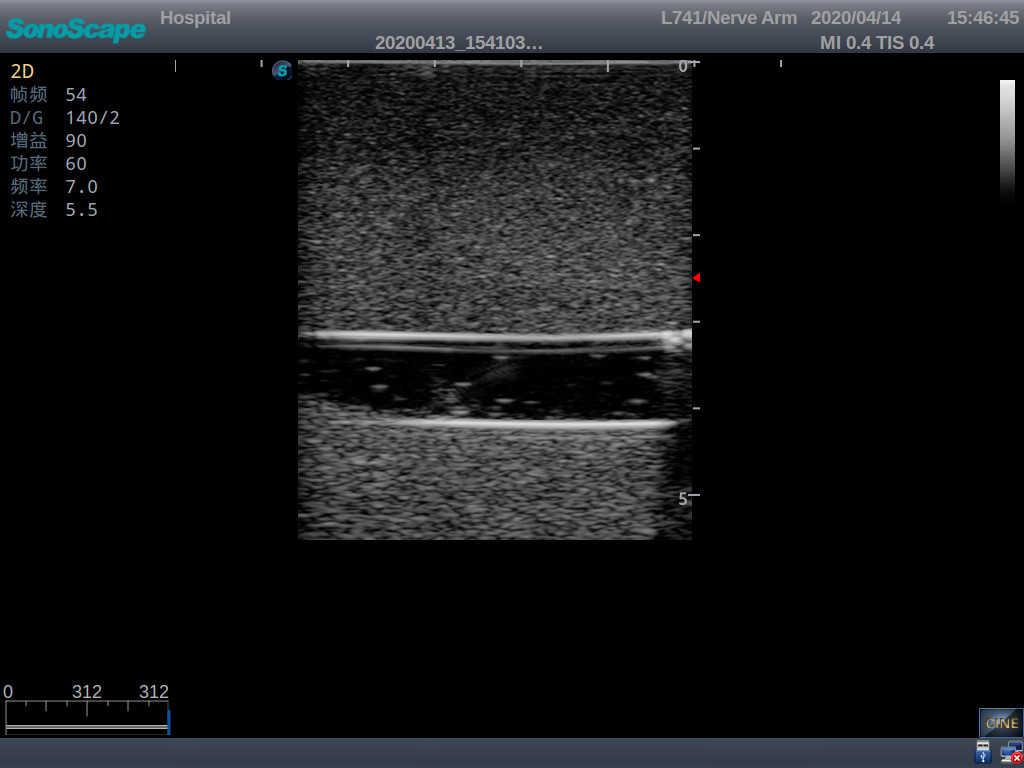

Model TYE1510.1

Outline

It is a model covering up from lobulus auriculae plane to the umbilical plane, and it has anatomical structures like clavicle, rib, sternocleidomastoid, jugular vein and basilic vein.

1)   Made of high molecular polymer ultrasound material, close to the real skin

2)   It can be used by real ultrasound machines

3)   Clear and real images of the tissues and organs (basilic vein and superior vena cava)